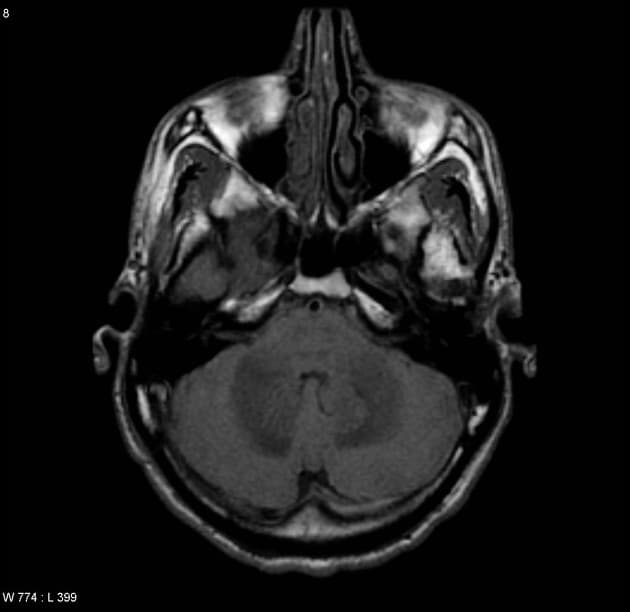

Chụp cộng hưởng từ (MRI) cho thấy các đặc điểm điển hình của bệnh xơ cứng rải rác. Ngoài ra, một số tổn thương có tín hiệu tăng trên hình ảnh T1 (T1 hyperintense).

Các phát hiện chính:

- Các tổn thương rải rác, dạng vệt hoặc hình tròn, tăng tín hiệu trên hình ảnh khuếch tán (diffusion-weighted imaging), khu trú chủ yếu ở vùng chất trắng quanh thất (periventricular white matter), chất trắng ở bán nguyệt (juxtacortical white matter), thân gai thị – giao thoa thị giác (optic radiation – optic chiasm), và thân não (brainstem) – phù hợp với đặc điểm của xơ cứng rải rác (multiple sclerosis).

- Một số tổn thương có tín hiệu tăng trên T1 (T1 hyperintense lesions) – gợi ý tổn thương mạn tính, liên quan đến mức độ tàn phế tăng và teo não (atrophy).

- Thể chai (corpus callosum) có tổn thương dạng dải ngang (Dawson's fingers) – đặc trưng của xơ cứng rải rác (multiple sclerosis).

- "Dawson's fingers là các tổn thương ở chất trắng quanh thất, định hướng vuông góc với não thất, đặc trưng cho xơ cứng rải rác."

- "Việc không có hạn chế khuếch tán, xuất huyết hay ngấm thuốc viền màng não giúp phân biệt xơ cứng rải rác với các bệnh viêm hoặc nhiễm trùng khác."